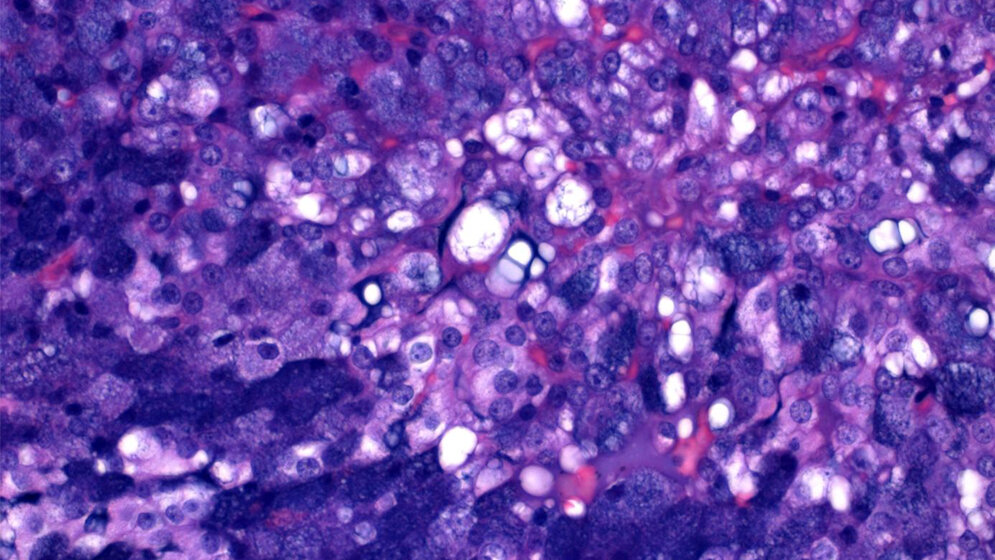

Dass die Forscher die molekularen Ursachen jetzt klären konnten, liegt dabei in der Kooperation mit anderen Instituten begründet, wie Stefan Wiemann vom Deutschen Krebsforschungszentrum, betont: „Unsere Studie zeigt, wie erfolgreich die Verknüpfung von molekularen und funktionellen Untersuchungen klinische Fragestellungen in einer engen wissenschaftlichen Zusammenarbeit zwischen großen Forschungsinstituten und klinischen Einrichtungen beantworten kann.“ Abbas Agaimy, Institut für Pathologie der FAU, fügt hinzu: „Die Ergebnisse dieser Studie verdeutlichen eindrucksvoll den Zusammenhang zwischen histomorphologischer Tumorerscheinung, also dem Phänotyp, und der zugrundeliegenden genetischen Veränderung, dem Genotyp. Bei der relativen Seltenheit von Speicheldrüsentumoren war diese Studie nur in Zusammenarbeit mit einer großen HNO-Klinik mit überregionalem exzellentem Ruf und hohen Patientenzahlen möglich.“ Und auch Matthias Bieg vom Berlin Institute of Health (BIH) sagt: „Diese Studie zeigt einmal mehr, wie wichtig es ist, Forscher aus verschiedenen Bereichen zusammenzubringen. Nur durch die fruchtbare Kooperation konnten wir die bestmöglichen Ergebnisse aus den zugrundeliegenden Daten extrahieren. Wir haben in dieser interdisziplinären Zusammenarbeit gezeigt, dass die Umlagerung von epigenetischen Kontrollelementen einen großen Einfluss auf die Entstehung von Tumoren haben kann.“ (DKFZ, red)